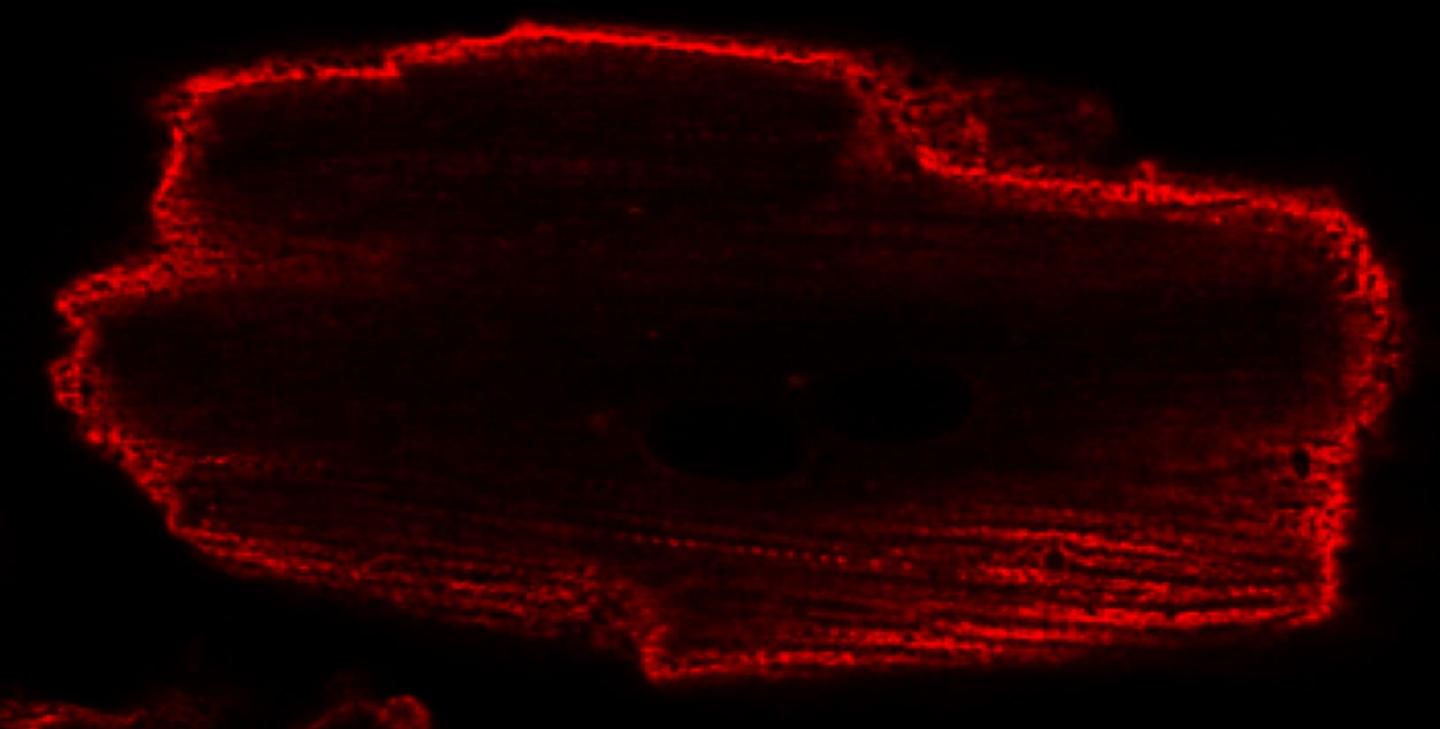

In particular, Scarlata's lab is exploring how certain G proteins play a role in regulating calcium levels within heart muscle cells (cardiomyocytes) and neurons. Using cultured cells that have properties related to heart tissue, Scarlata has found that mechanical stimuli, such as the stretching and relaxing of muscle cells, affect the release of G proteins from the cell membrane. That G protein activity, in turn, can cause wavelike changes in the concentration of calcium in the cell interior. The movement of calcium in and out of the cell interior plays a role in the contraction of the heart muscle and the transmission of signals along neurons.